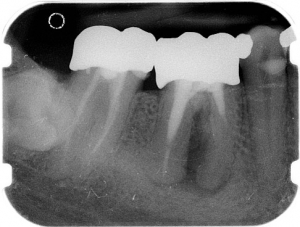

Die Wurzelkanal-Füllung ist notwendig, um Bakterien keinen Raum für eine erneute Ausbreitung zu bieten. Wir verarbeiten die Guttapercha ausschließlich thermoplastisch, also in einem recht aufwendigen Verfahren, bei dem das Material durch Wärme fließfähig gemacht und dann in die Hohlräume verpresst wird. So entsteht die bestmögliche Versiegelung der Hohlräume. Die Aufbereitungstiefe und das Behandlungsergebnis werden mittels Röntgenbildern kontrolliert und dokumentiert.